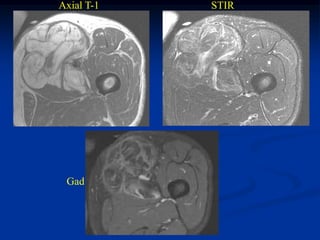

Case #314.1             Angiosarcoma Thigh

52 yr old male with

tender mass in proximal

anterior thigh area 3 mos

Axial T-1   STIR

Cor STIR   Sag STIR